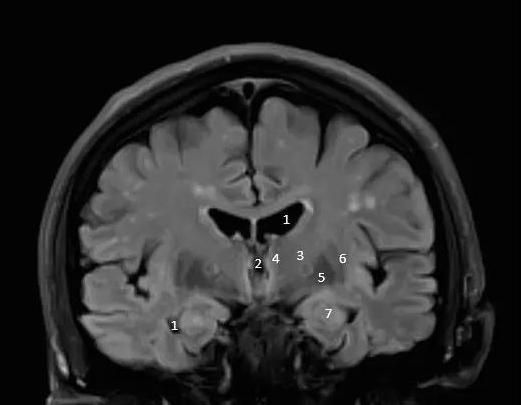

双侧侧脑室

双侧侧脑室,侧脑室位置图片

侧脑室位置图片

侧脑室图片

侧脑室磁共振

侧脑室解剖

侧脑室与第三脑室图解

侧脑室解剖图

侧脑室三角区图片